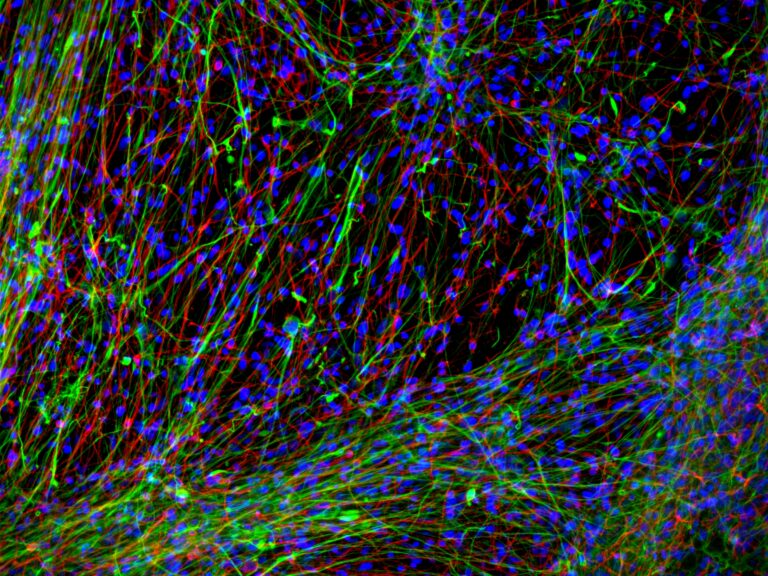

Stevens Rehen é um neurocientista do Instituto D’Or de Pesquisa e Ensino (IDOR) no Brasil e atua como Pesquisador Associado na Promega Corporation e no Instituto Usona. Ele é Membro Afiliado da Academia de Ciências da América Latina e da Academia de Ciências do Mundo em Desenvolvimento (TWAS). Entre suas honrarias estão a Ordem Nacional do Mérito Científico (Comendador, Brasil) e a Bolsa do Programa Latino-Americano PEW em Ciências Biomédicas. Ele detém um cargo não remunerado de professor na Universidade Federal do Rio de Janeiro e foi reconhecido com o Prêmio Internacional Fiocruz Servier para Neurociências e o Prêmio Fulbright de Professor Visitante. Stevens Rehen também foi Presidente da Sociedade Brasileira de Neurociências e Comportamento. Seu foco principal de pesquisa é sobre os efeitos dos psicodélicos em organoides cerebrais humanos e Caenorhabditis elegans.

N. Costa M, Goto-Silva L, M. Nascimento J, Domith I, Karmirian K, Feilding A, Trindade P, Martins-de-Souza D, K. Rehen S. LSD Modulates Proteins Involved in Cell Proteostasis, Energy Metabolism and Neuroplasticity in Human Cerebral Organoids. ACS Omega. (2024).

Ornelas IM, Cini FA, Wießner I, Marcos E, Araújo DB, Goto-Silva L, Nascimento J, Silva SRB, Costa MN, Falchi M, Olivieri R, Palhano-Fontes F, Sequerra E, Martins-de-Souza D, Feilding A, Rennó-Costa C, Tófoli LF, Rehen SK, Ribeiro S. Nootropic effects of LSD: Behavioral, molecular and computational evidence. Exp Neurol. 2022 Oct;356:114148. doi: 10.1016/j.expneurol.2022.114148. Epub 2022 Jun 19. PMID: 35732217.

Dakic V, Minardi Nascimento J, Costa Sartore R, Maciel RM, de Araujo DB, Ribeiro S, Martins-de-Souza D, Rehen SK. Short term changes in the proteome of human cerebral organoids induced by 5-MeO-DMT. Sci Rep. 2017 Oct 9;7(1):12863.